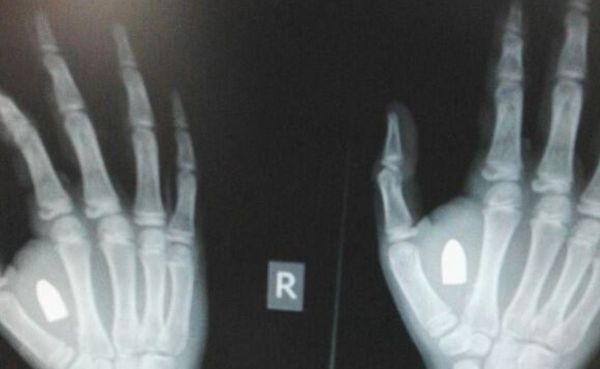

הזוי: ילד התלונן על נפיחות, הרופאים מצאו ביד קליע

ילד בן 12 הובא למיון בירושלים לאחר שהתלונן חודשים על כאבים ונפיחות בכף יד ימין. צילום הרנטגן הראה קליע כלוא בתוך ידו. ההורים: "לא יודעים איך הוא הגיע לשם"